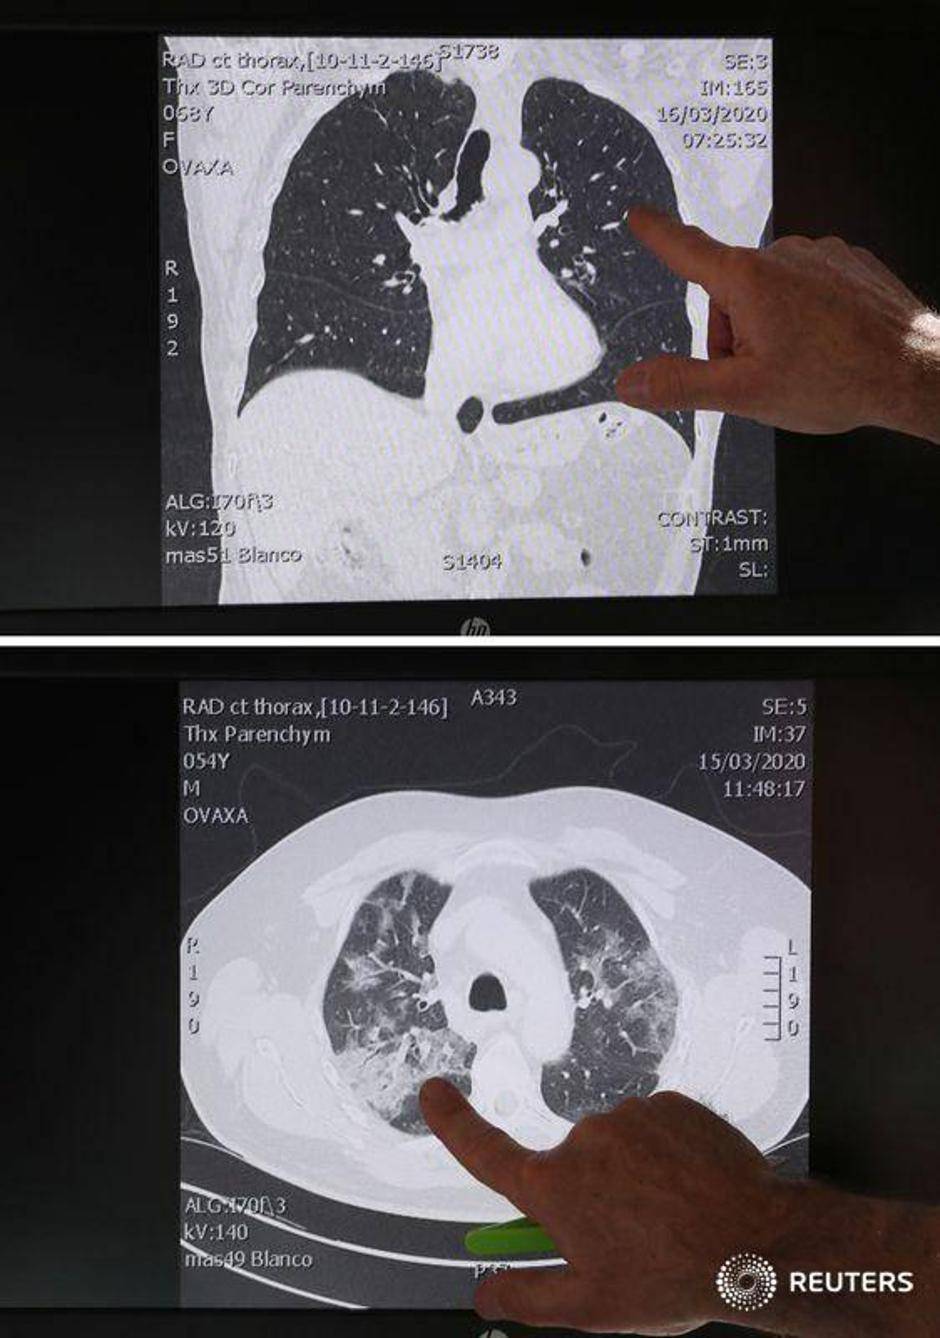

U međuvremenu, liječnik hitne pomoći u Belgiji otkrio je šokantne slike pluća 'mladih, zdravih ljudi', koje je opisao kao 'ništa strašno'. Ignace Demeyer, također je upozorio da nitko nije izuzetak što se tiče zaraze virusom.

Doktor Demeyer također je pokazao nedavne snimke pluća pacijenta s koronavirusom. U pitanju su bili mladi ljudi koji su se bavili sportom.

Prva pretraga pokazuje normalna, zdrava pluća. Drugi prikazuje vreće zraka u plućima ispunjene upalnom tekućinom, što je na trećoj slici vidljivo.

- Ti ljudi se naravno mogu još izliječiti, ali to je opasna situacija po život. A oni su ljudi koji ne puše, nemaju dijabetes ili probleme sa srcem. Oni su sportski mladi ljudi - dodao je liječnik.